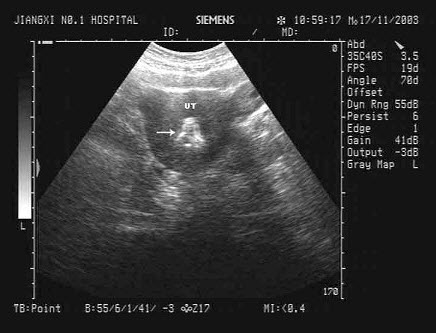

74、单项选择题

患者,男性,70岁,出现无痛性血尿,如图所示,该病例最可能的诊断为()

A.膀胱结石

B.膀胱血块

C.膀胱异物

D.膀胱肿瘤

E.前列腺增生